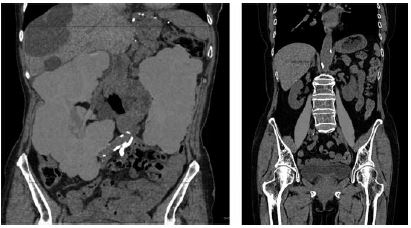

もう一つ、臓器認識ツールというのも使用できる。現在のツールでは肺野、肝臓、腎臓、脾臓、大腰筋、骨の領域を認識し、その容積を自動計測できる。たとえば多発嚢胞腎の進行度や予後を判定するのに腎容積を測定する事がある(図6a)。これまではMPR画像による簡易法やWorkstationでの計測が必要であったが、瞬時に計測できるためレポート内に反映させやすい。また大腰筋全体の筋肉量測定が瞬時に可能であり、近年注目されているサルコペニアの診断にも有用になるだろう(図6b)。